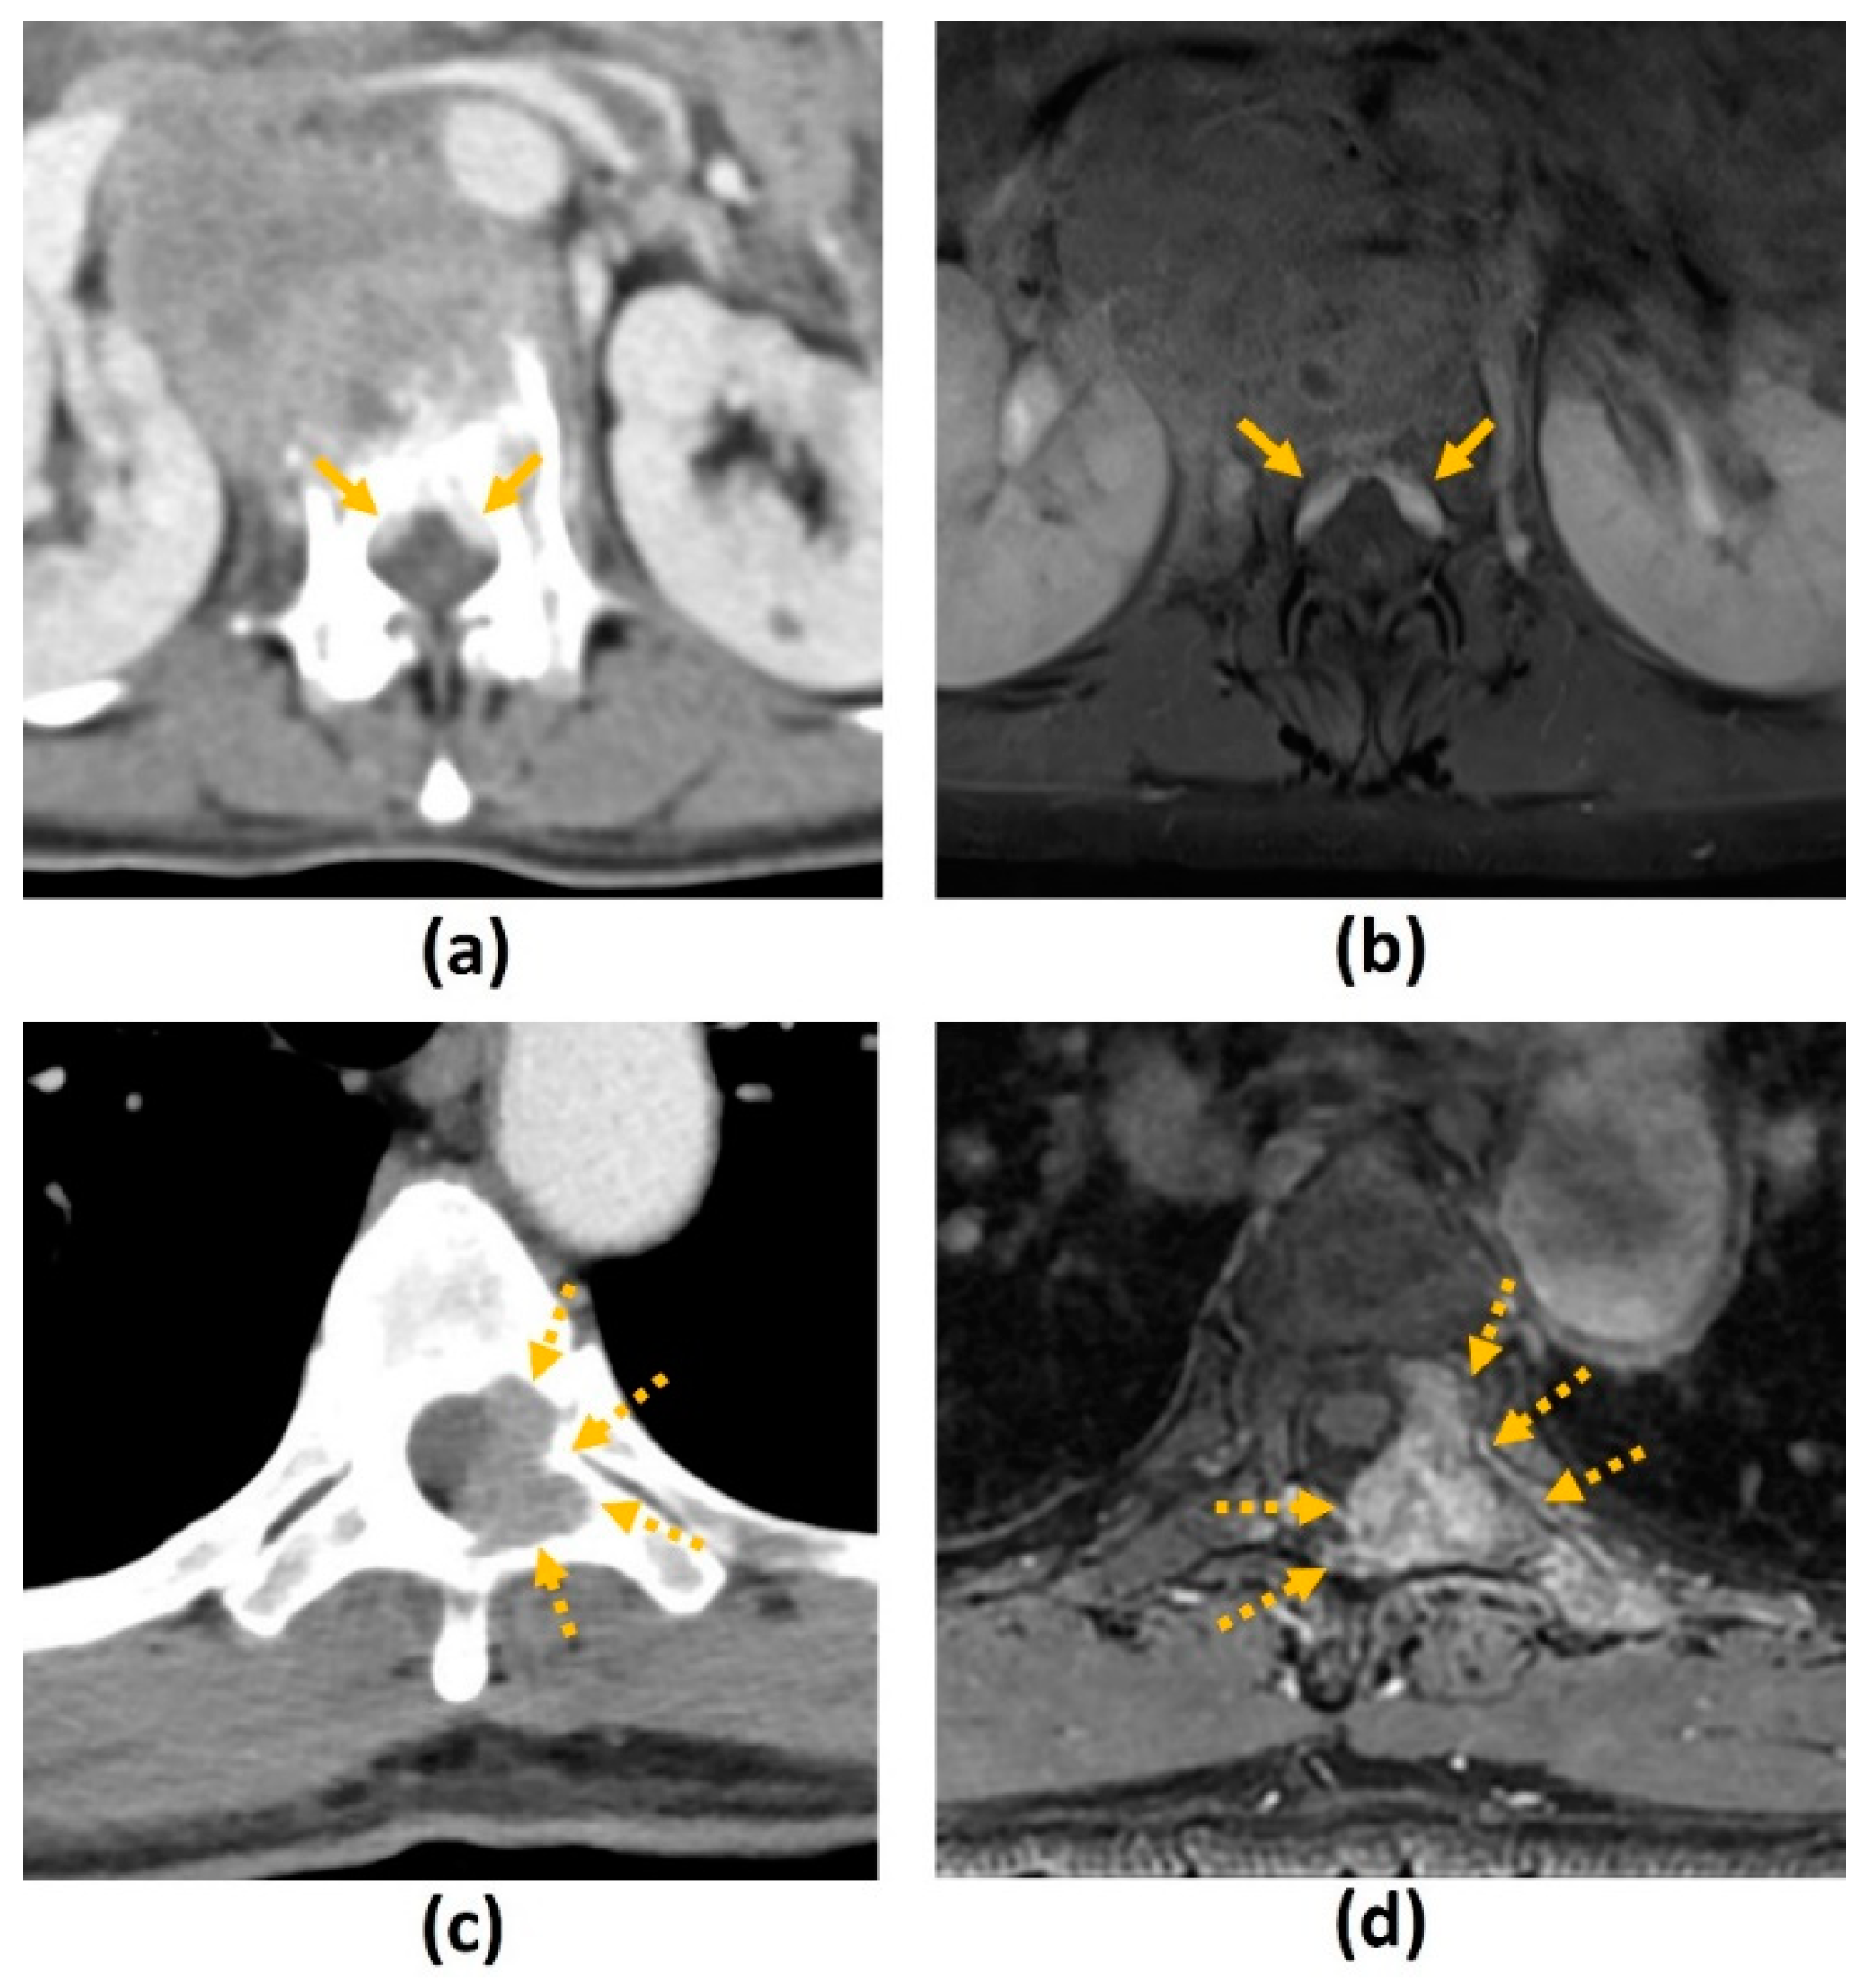

3.3. Computed Tomography (CT) Myelogram

- MRI is contraindicated (e.g., due to extreme claustrophobia, large body habitus, inability to lie still for a prolonged period of time, metallic foreign body in orbit, or a noncompatible cardiac device);

- Poor diagnostic yield of MRI due to metal artifacts from spinal implants (CT will also require MAR techniques);

- Patel, D.M.; Weinberg, B.D.; Hoch, M.J. CT Myelography: Clinical Indications and Imaging Findings. Radiographics 2020, 40, 470–484. [Google Scholar] [CrossRef]

- Hollis, P.H.; Malis, L.I.; Zappulla, R.A. Neurological deterioration after lumbar puncture below complete spinal subarachnoid block. J. Neurosurg. 1986, 64, 253–256. [Google Scholar] [CrossRef]

- Hagenau, C.; Grosh, W.; Currie, M.; Wiley, R.G. Comparison of spinal magnetic resonance imaging and myelography in cancer patients. J. Clin. Oncol. 1987, 5, 1663–1669. [Google Scholar] [CrossRef] [PubMed]

- Loblaw, D.A.; Perry, J.; Chambers, A.; Laperriere, N.J. Systematic review of the diagnosis and management of malignant extradural spinal cord compression: The Cancer Care Ontario Practice Guidelines Initiative’s Neuro-Oncology Disease Site Group. J. Clin. Oncol. 2005, 23, 2028–2037. [Google Scholar] [CrossRef] [PubMed]